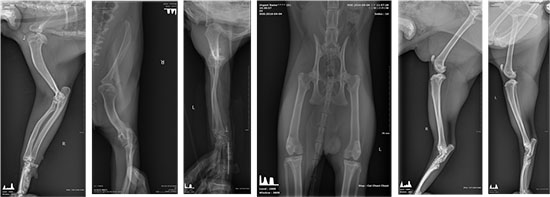

△영상검사

• X-ray

- 어깨관절 양측 탈구(후방탈구), 내외측 탈구는 없음

- 고관절 : 미약한 고관절 이형성

- 전반적으로 미약한 골관절염의 소견은 있으나 골의 증식 소견은 없음

• Dx

- 골연골이형성증

- 어깨관절탈구

- 관절염